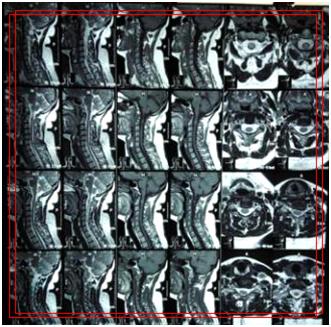

(颈段海绵状血管瘤)